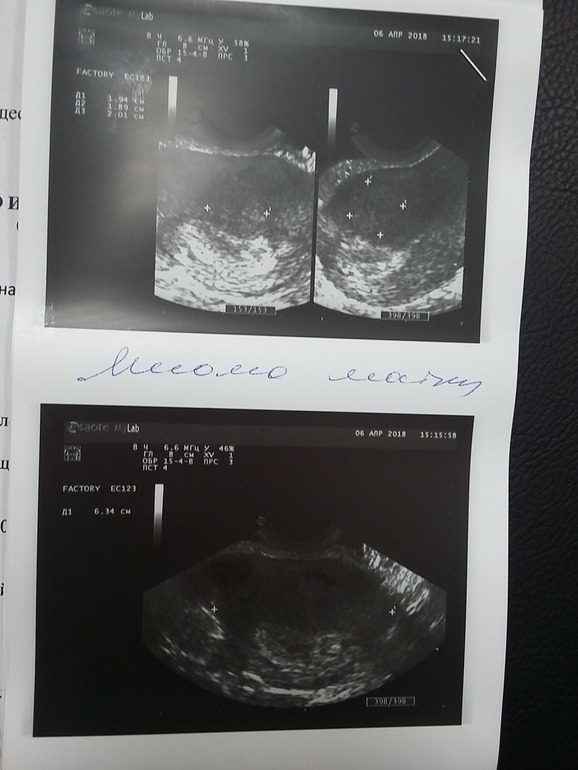

Странно то, что мне сейчас ставят гематому. Но когда я была на узи 1.5 недели назад, у меня была миома. Сейчас эта узист говорит, что никакой миомы она не видит.

Вот мое прошлое заключение с узи

Видимо какой то врач ошибается? Или как?